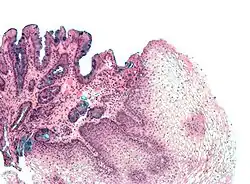

L'epitelio di Barrett oppure esofago di Barrett è una metaplasia, un adattamento delle cellule della parte inferiore dell'esofago ad uno stimolo nocivo. Esso è caratterizzata dalla sostituzione del normale rivestimento dell'epitelio squamoso pluristratificato dell'esofago in epitelio colonnare semplice con cellule mucipare caliciformi (che si trovano di solito nel tratto gastrointestinale). Il significato medico dell'esofago di Barrett è la chiara correlazione (circa 0,5% per anno-paziente) con l'adenocarcinoma esofageo, un tumore molto spesso mortale,[1][2] per cui è considerata una condizione precancerosa.

Le cellule che sostituiscono il tratto di epitelio esofageo che viene a contatto con il reflusso acido hanno caratteristiche molto simili a quelle intestinali e costituiscono l'esofago di Barrett. Questo cambiamento nel programma di differenziamento delle cellule staminali (non si sa ancora l'esatta natura ed origine di questi elementi staminali) della mucosa esofagea viene definito metaplasia, cioè una modificazione per cui un tipo cellulare differenziato viene sostituito da un altro tipo cellulare differenziato. Posta per buona la definizione di esofago di Barrett inteso come metaplasia intestinale, è possibile classificarlo in tre sotto-istotipi: "tipo I" o metaplasia intestinale completa, contenente cellule di Paneth, caliciformi e cellule assorbenti (è un tipo raro); "tipo II", quadro ghiandolare misto con cellule foveolari gastriche e cellule caliciformi mucipare; "tipo III", fatto da sole cellule caliciformi. L'epitelio cilindrico così originatosi è più resistente al danno indotto dalla pepsina e dall'acido di quanto lo sia quello squamoso.